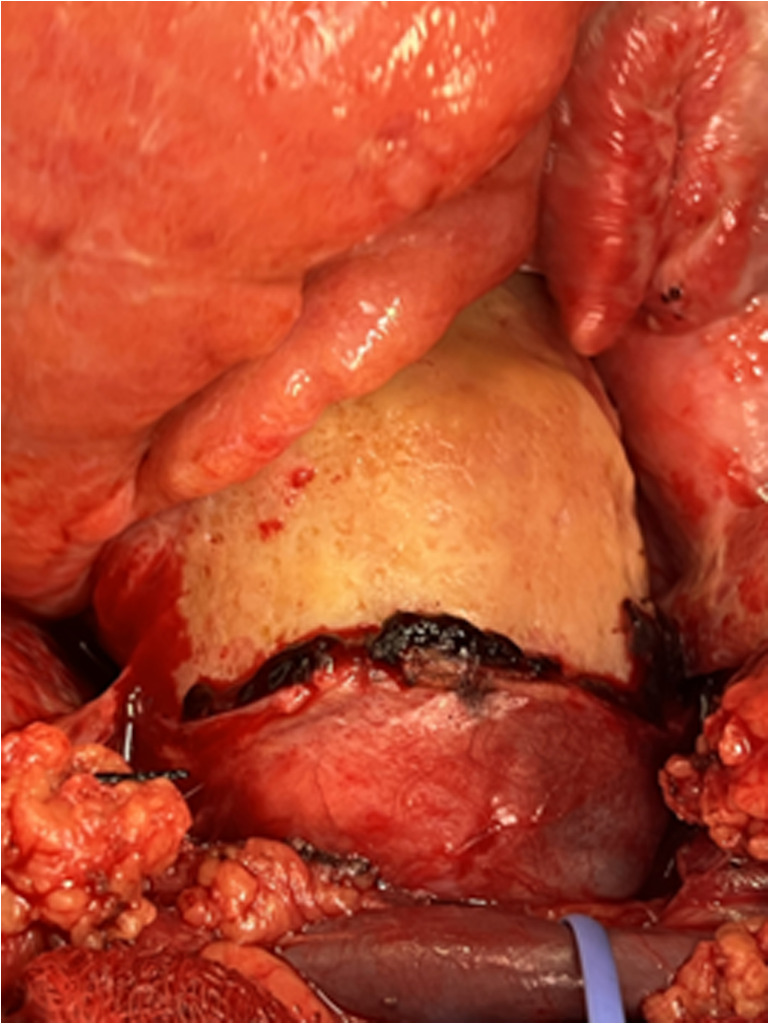

Systemic lupus erythematosus (SLE) is a chronic autoimmune disorder with diverse clinical manifestations. While small vessel vasculitis is a common SLE complication, lupus aortitis is an exceedingly rare entity with limited documentation. Here, we report a novel case of lupus aortitis misleadingly appearing on imaging studies as an aortic intramural hematoma in a 68-year-old male. The patient initially exhibited fatigue, dyspnea, and pericardial effusion. Imaging studies suggested an intramural hematoma of the ascending aorta and the aortic arch, prompting urgent surgical exploration. Intraoperative findings revealed a thickened, fibrotic, and heavily calcified aorta (egg-shell aorta) without hematoma. Subsequent histopathological and immunological analyses confirmed lupus aortitis. This case underscores the diagnostic challenges posed by this rare SLE complication, which can mimic other aortic pathologies. Early recognition and individualized treatment are paramount. Further studies are needed to elucidate its pathophysiology and establish standardized management guidelines.